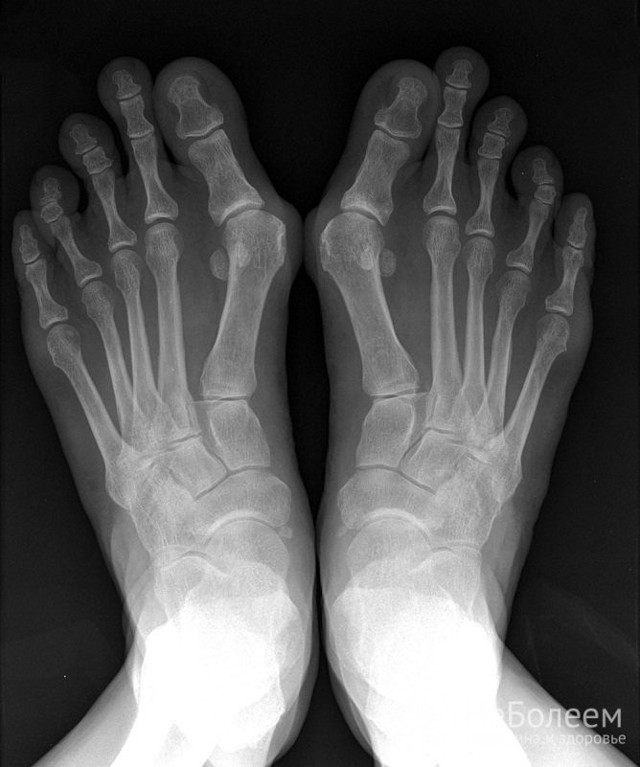

При полиартрите поражаются пять и более суставов

Вальгусные деформации больших пальцев рук и ног дают основание заподозрить подагрический артрит, а в случае псориатического артрита сильно деформируются и утолщаются суставы кисти.

Ревматоидная стопа

При ревматоидном артрите воспаление суставов симметричное, в большинстве случаев начинается с сочленений кистей и стоп. Позже возникают разрастания синовиальной оболочки и остеофиты, что ведет к деформации суставов.

Подагра — воспаление суставов может протекать в острой или хронической форме. Для острого подагрического артрита характерно асимметричное поражение первого плюснефалангового сустава с выраженным болевым синдромом.